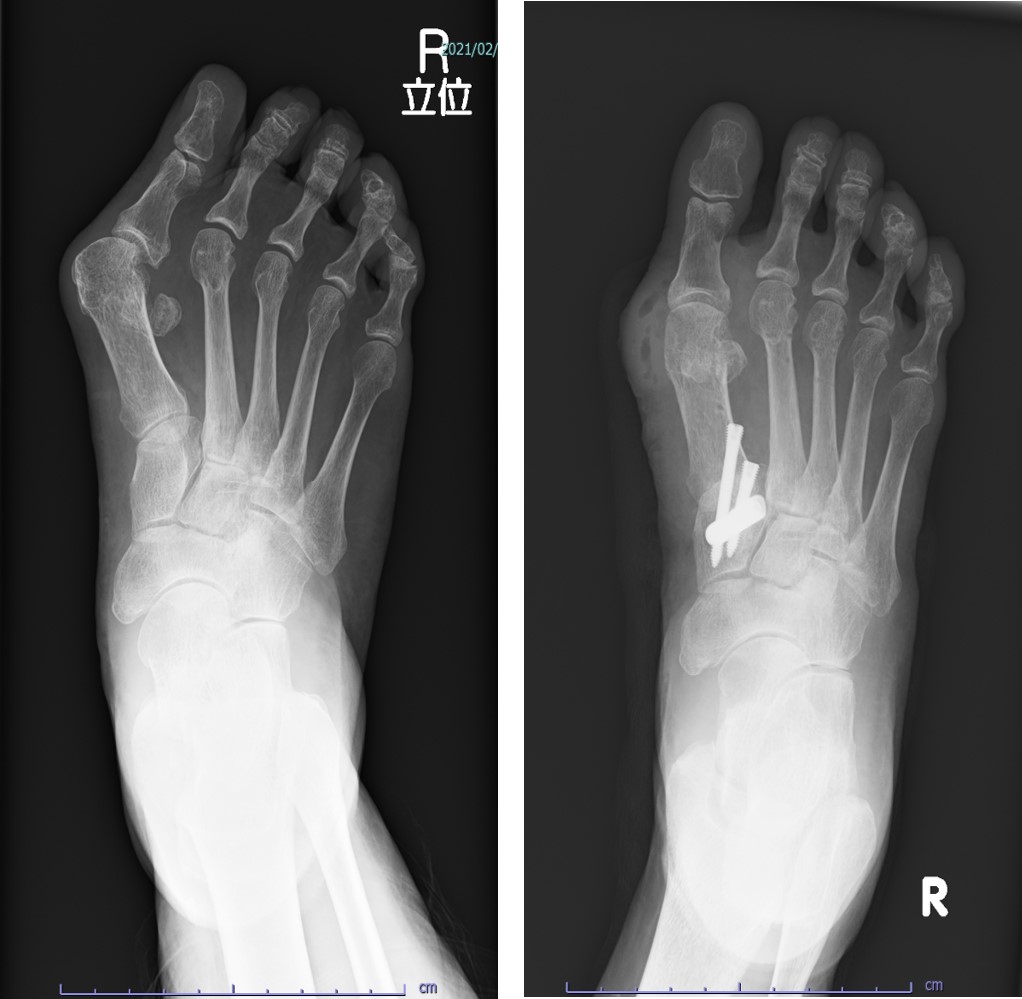

外反母趾や足趾変形をあきらめないで、ご相談してください。